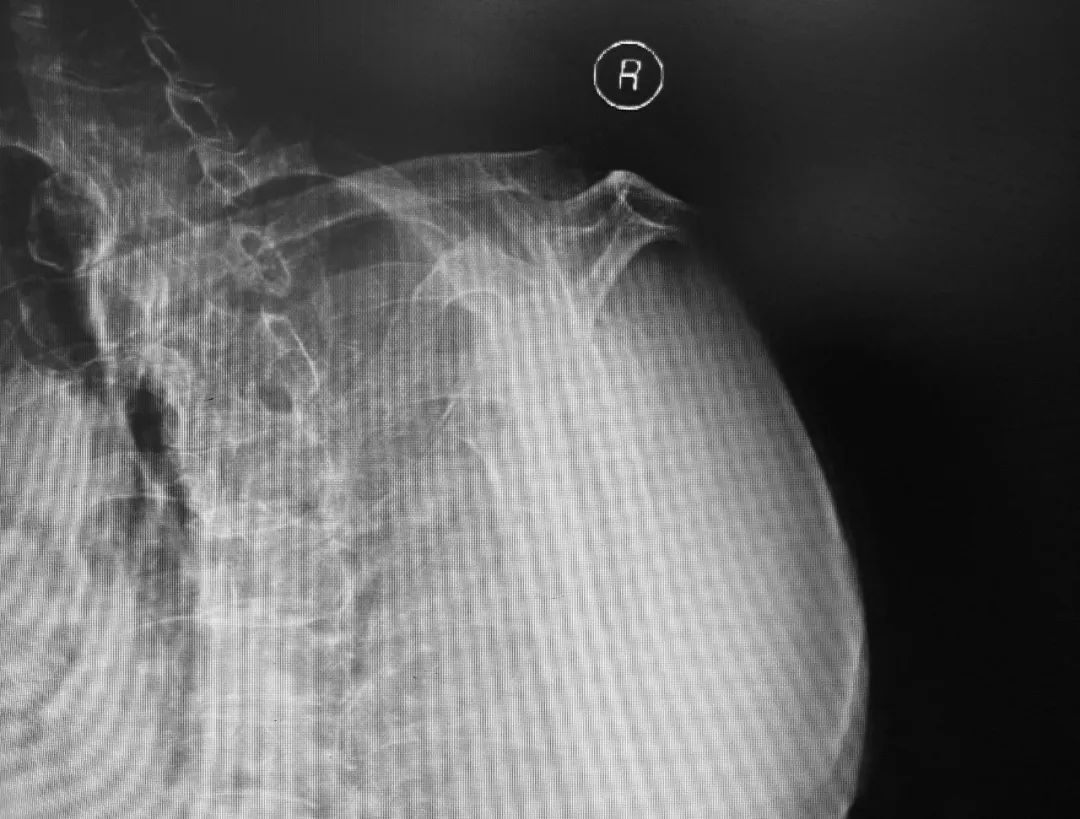

患者女性,72岁,不幸在两周前因骑车摔伤导致右侧肱骨近端粉碎性骨折,外院予其支具固定、保守治疗。为了尽快缓解骨折带给自己的痛苦,并寻求更好的远期功能结果,患者来到积水潭医院寻求救治。蒋协远院长带领的智能骨科团队经过仔细查体和阅读影像资料,共同商讨该病例后,蒋院长认为本患者年龄较大,平时身体状态良好、基础病不多,加之患者自己手术意愿较为强烈,决定为她实行机器人辅助下的反式人工肩关节置换术。

术前,患者的影像资料。